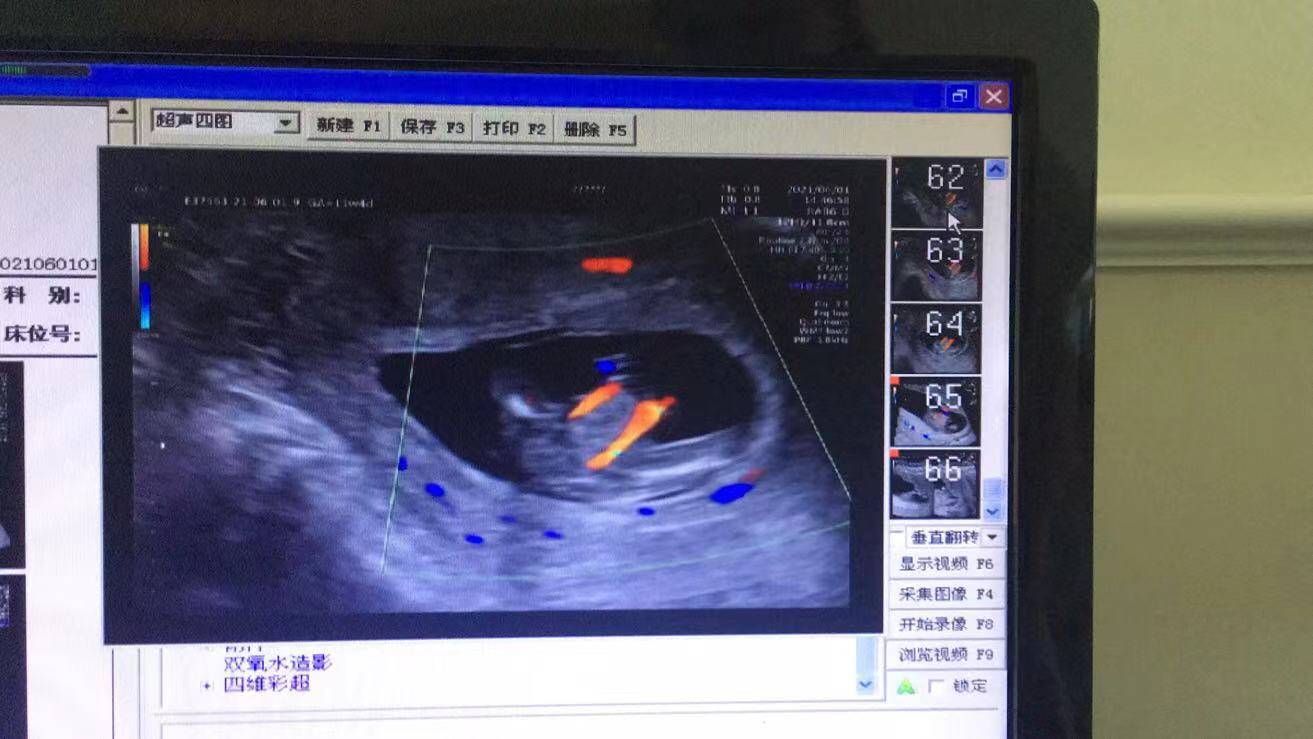

原來,前幾天,懷孕11周的她來到武漢仁愛醫(yī)院超聲科做了NT(頸項透明層)檢查,發(fā)現(xiàn)腹中胎兒有些異樣,寶寶的右腳缺失,脊柱部也有異常,超聲科醫(yī)生立刻叫來了超聲科王娟主任進(jìn)行再次檢查,經(jīng)過30分鐘的仔細(xì)探查后,王主任終于看清楚了胎兒的情況,并最終確診:“腹中胎兒右小腿長骨發(fā)育不良,右腳缺失,脊柱腰骶段排列異常,會陰部包塊,考慮泄殖腔外翻可能。”王娟介紹。

(王女士NT檢查結(jié)果)